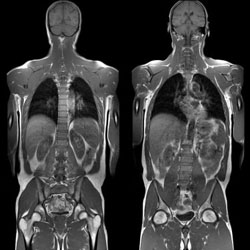

MRI az egész test a primer diagnózisa szervek és szövetek a szervezetben azonosítása érdekében, és lokalizálja a tumor, a jelenléte súlyos elváltozások a belső szervek és szövetek, ha lehetetlen meghatározni a betegség oka. A szállító által a szűrési eljárást több síkban.

A fő előnye az eljárásnak, így azonnal a teljes mennyiségű információt az állam a szervezet egésze és az azt alkotó osztályok különösen. Ez a fajta MRI írják, ha sürgősen szüksége van a pontos diagnózis a rákkutatás, ha diagnosztizáltak zárt sérülés egyéni jelzéseket.

A kezelés az egész test MRI tartalmazza a tanulmány az alábbi területeken:

MRI nagyon pontos és biztonságos, nem sugárterhelés, nem kell külön készülni a találkozón. A beavatkozás előtt távolítsa el az összes elem és ruházati fém elemek vannak halmozva a kanapéra, amely belép a jármű alagúton. Fekvő továbbra is szükség van, hogy egy világos képet. Időtartam 30 perc - óra. A diagnózis után a beteg és a képekhez szakmai megítélés. Ha szükséges, a tanulmány szerint mellékelt lemezen.